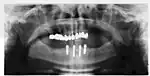

Success or failure of implants depends primarily on the thickness and health of the bone and gingival tissues that surround the implant, but also on the health of the person receiving the treatment and drugs which affect the chances of osseointegration. The amount of stress that will be put on the implant and fixture during normal function is also evaluated. Planning the position and number of implants is key to the long-term health of the prosthetic since biomechanical forces created during chewing can be significant. The position of implants is determined by the position and angle of adjacent teeth, by lab simulations or by using computed tomography with CAD/CAM simulations and surgical guides called stents. The prerequisites for long-term success of osseointegrated dental implants are healthy bone and gingiva. Since both can atrophy after tooth extraction, pre-prosthetic procedures such as sinus lifts or gingival grafts are sometimes required to recreate ideal bone and gingiva.

When a more exacting plan is needed beyond clinical judgment, the dentist will make an acrylic guide (called a stent) prior to surgery which guides optimal positioning of the implant. Increasingly, dentists opt to get a CT scan of the jaws and any existing dentures, then plan the surgery on CAD/CAM software. The stent can then be made using stereolithography following computerized planning of a case from the CT scan. The use of CT scanning in complex cases also helps the surgeon identify and avoid vital structures such as the inferior alveolar nerve and the sinus.[32][33]: 1199